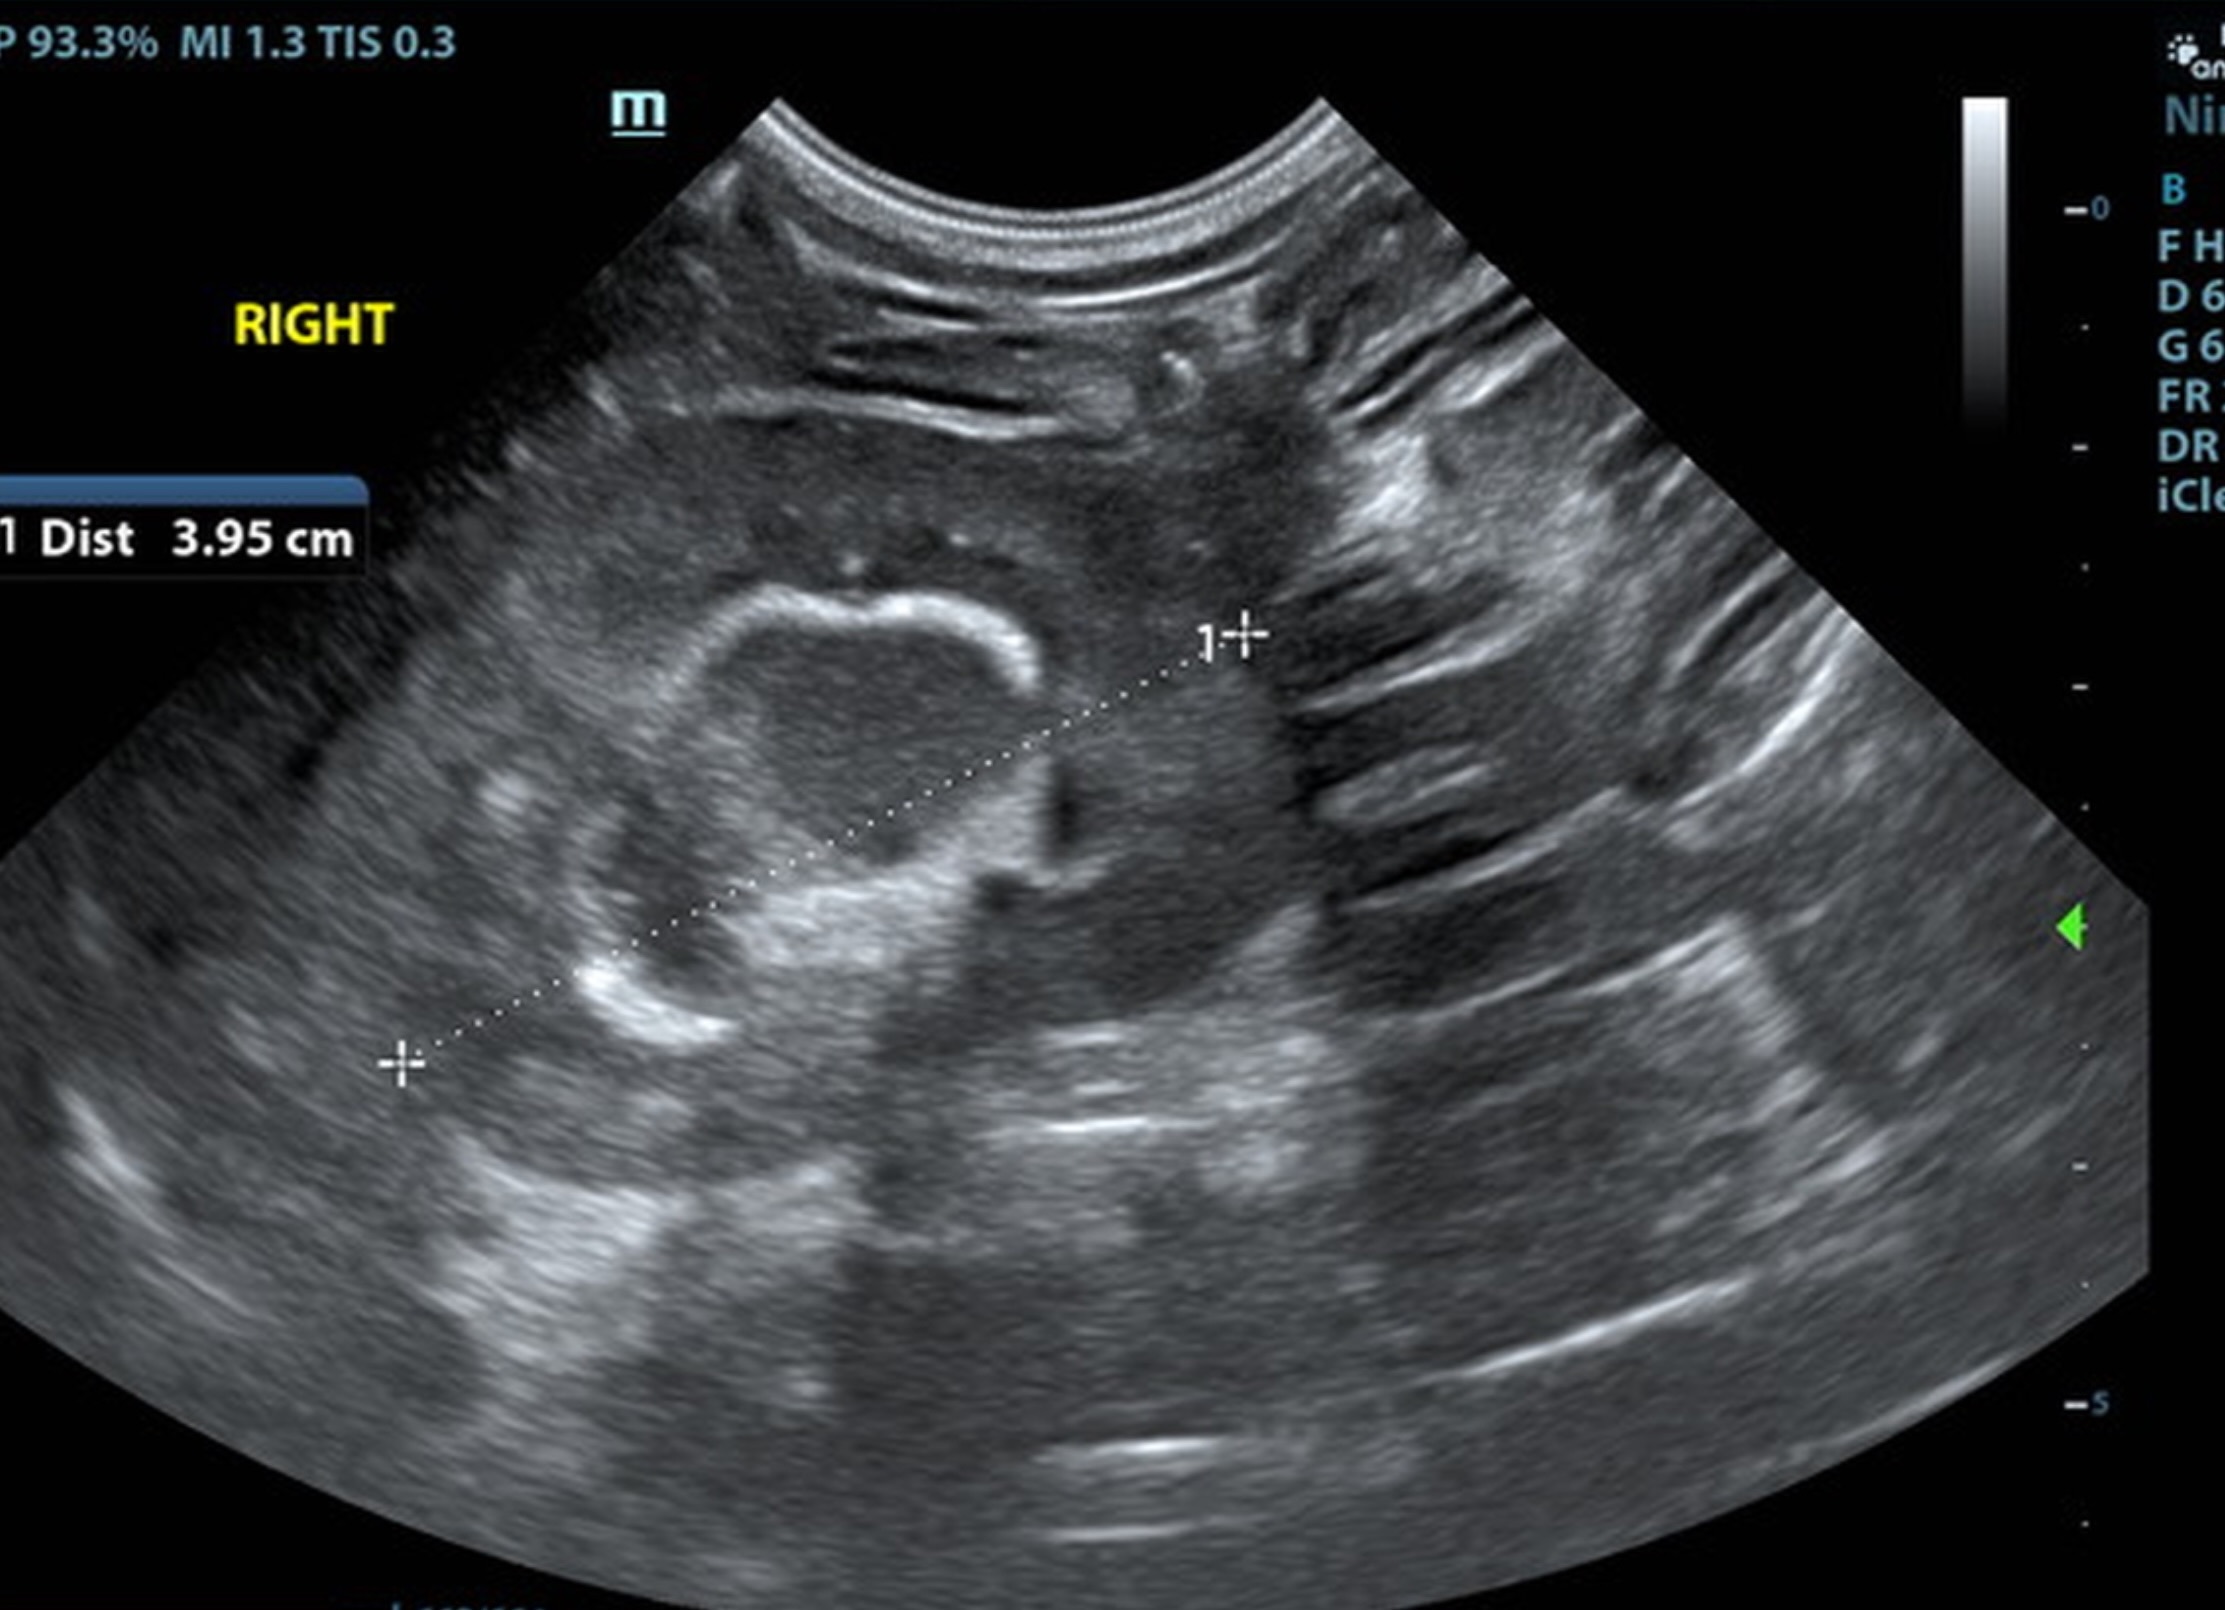

The kidneys were swollen with hyperechoic, mineralized medullary rim sign. The right kidney measured 4.0 cm. The left kidney measured 3.95 cm.